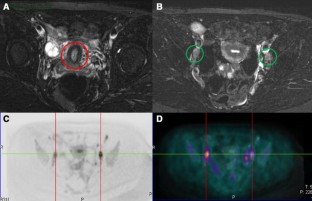

The aim of this study was to compare the accuracy of retrospective image fusion of PET/MRI-DWI with that of PET/CT and MRI-DWI alone in detecting metastatic lymph nodes in patients with cervical and endometrial carcinoma.

On a per-patient basis PET/MRI-DWI had the same sensitivity (87.5 %), specificity (84.2 %), diagnostic accuracy (85.1 %), PPV (70 %), and NPV (94.1 %) as PET-CT, but on a per-node basis PET/MRI-DWI showed better sensitivity (89 vs 70.2 %), specificity (91.6 vs 90.5 %), diagnostic accuracy (91.2 vs 87 %), PPV (68.7 vs 60.4 %), and NPV (97.6 vs 93.6 %) than PET-CT. Comparison of the areas under the ROC curves for the detection of metastatic lymph nodes demonstrated a non-significant difference (p = 0.055) between PET/CT and fused PET/MRI-DWI.

PET/MRI-DWI may be a valuable technique for N-staging patients with endometrial and cervical cancer, but more studies are needed to investigate its potential clinical utility.